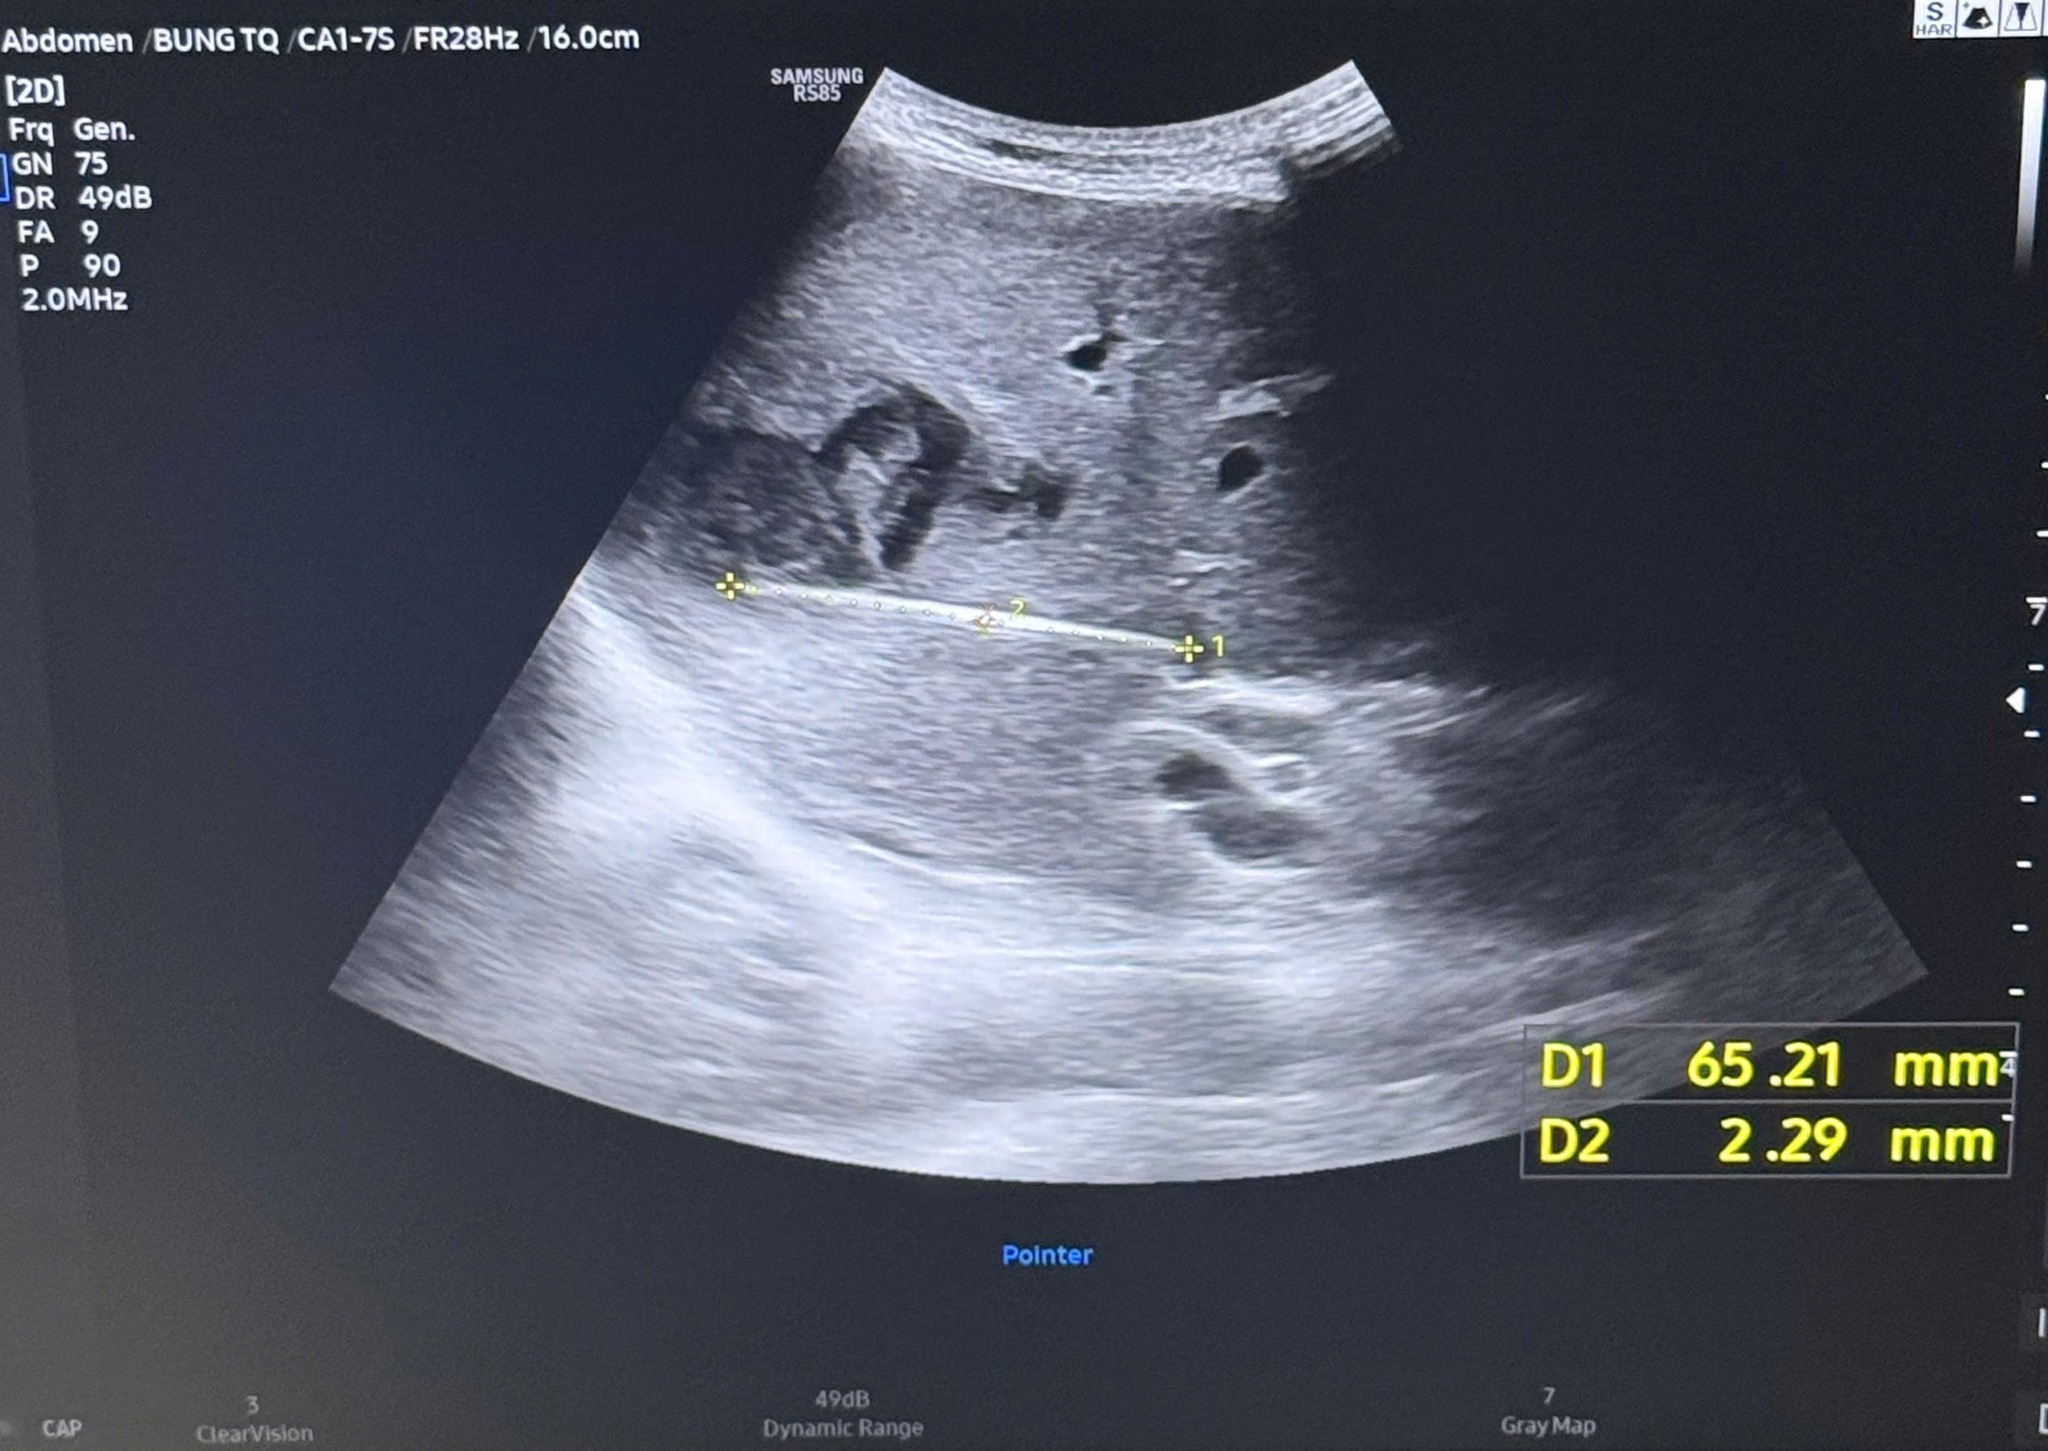

Cây tăm được bác sĩ gắp ra (bên trái) và hình ảnh cây tăm qua siêu âm (bên phải)

Qua thăm khám lâm sàng và siêu âm bụng, các bác sĩ phát hiện bệnh nhân có ổ áp xe gan. Tuy nhiên, ổ áp xe nằm khá sâu trong nhu mô gan, biểu hiện không điển hình nên bệnh nhân được chỉ định nhập viện để thực hiện thêm các cận lâm sàng chuyên sâu.

Khi tiến hành siêu âm chi tiết hơn, ê-kíp điều trị phát hiện một dị vật cản quang xuyên trong nhu mô gan, dài khoảng 6–7cm. Kết quả chụp cắt lớp vi tính (CT scan) ổ bụng sau đó xác định có một dị vật dạng que dài nằm hoàn toàn trong gan, kèm theo ổ áp xe sâu.